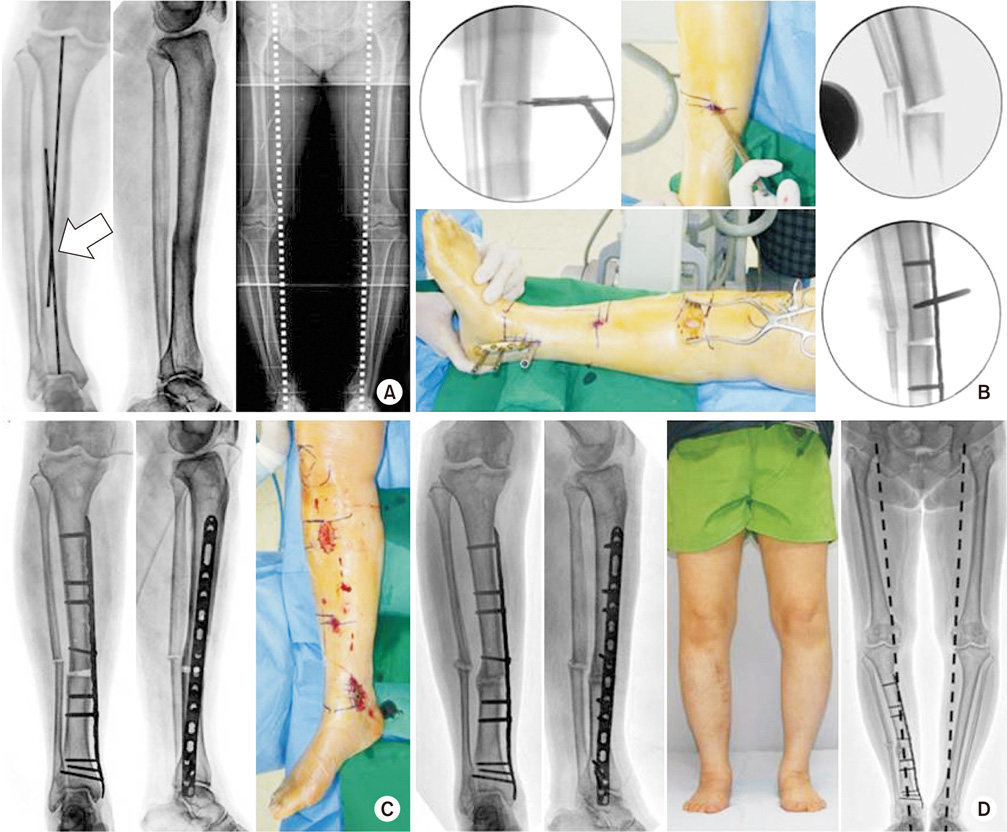

Fig. 1

(A) A 24-year-old male underwent plate fixation due to fracture of the tibia, but angulation and displacement remained. After 12 years of injury, the bone was united. (B) A slight shortening of the lower limb and medial deviation of the mechanical axis were checked, and traumatic osteoarthritis was found in the medial compartment of the left knee compared to the right knee (arrow).

jkfs-30-219-g001.jpg

Fig. 1 (A) A 24-year-old male underwent plate fixation due to fracture of the tibia, but angulation and displacement remained. After 12 years of injury, the bone was united. (B) A slight shortening of the lower limb and medial deviation of the mechanical axis were checked, and traumatic osteoarthritis was found in the medial compartment of the left knee compared to the right knee (arrow).